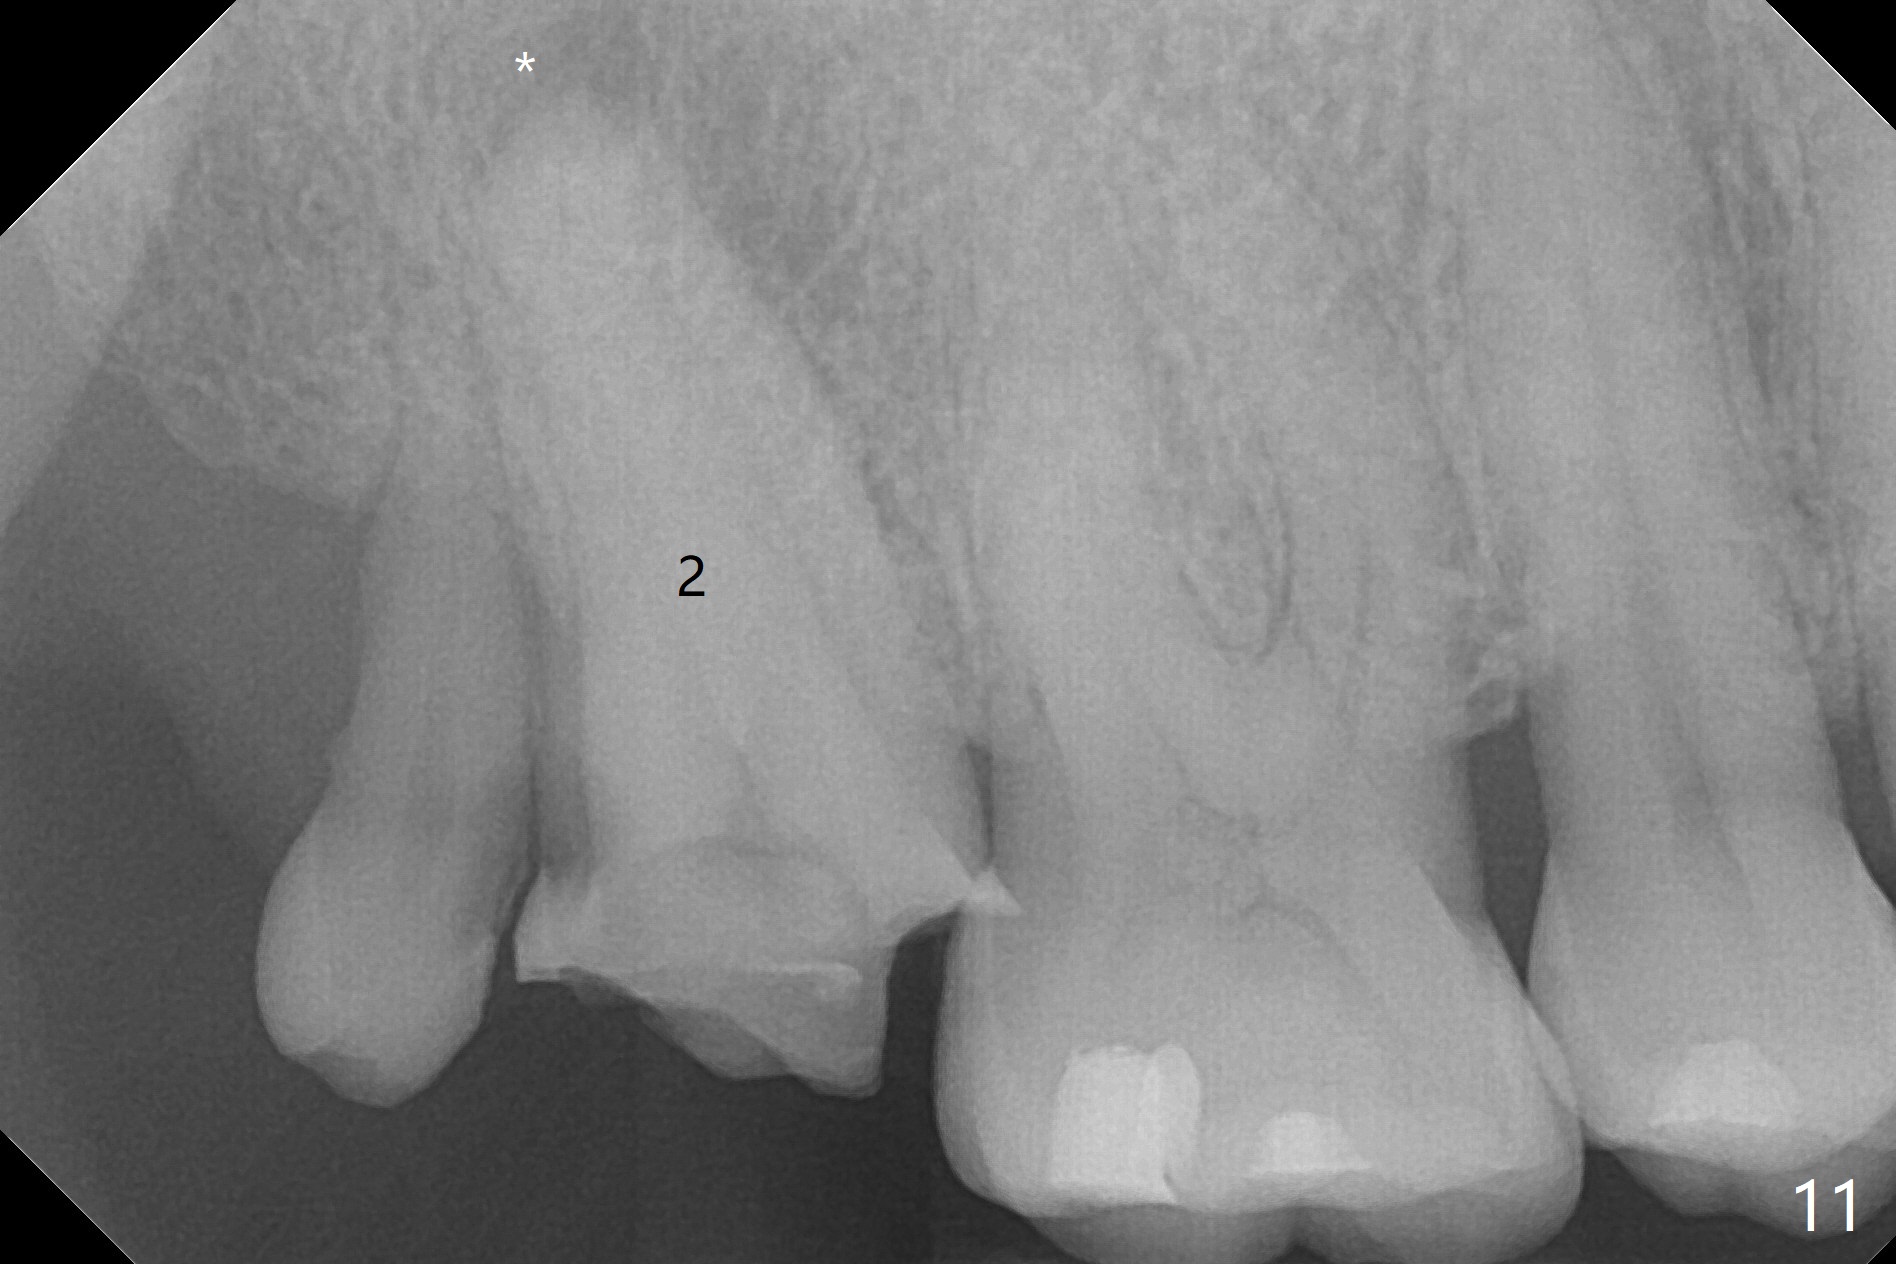

When the residual roots of the tooth #30 (Fig.1) are removed, the buccal crest is found ~ 2 mm apical to the lingual one (Fig.2 <); while the initial depth of osteotomy is 11.5 mm (yellow lines), the parallel pin is 10 mm long.  To place a 5x11.5 mm implant at the level of the buccal crest (Fig.4 (>45 Ncm)), subsequent osteotomy depth is 13 mm using the lingual crest as a landmark (Fig.3 (4 mm drill in place)).  After insertion of a 5.7x5.5(3) mm abutment, Vanilla Graft is placed (Fig.5 * with 2 mm buccal gap).  The abutment with a provisional is loose 4 months postop (Fig.6).   The permanent restoration is cemented 6 months postop.  The abutment screw is loose and fractured 8 and 11 months post cementation, respectively (Fig.7).  The fractured screw seems to be loose within the implant well and is easily re-winded out using Screw Removal Kit (sr-kit.html).  When the crown/abutment at #30 is loose 2nd time 1 year 7 months post cementation (Fig.8 taken post retightening), the screw at #19 fractures.  The tooth #2 needs a crown.  The patient cannot use the anterior teeth, since the teeth #8 and 9 have root fracture.  Can extraction and bone graft increase bone height?  The screw re-fractures 9 months later (Fig.9).  The dislodged crown is sectioned; the abutment is reseated completely (Fig.10) for a new crown. The tooth #2 needs RCT, B-U and crown, while the tooth #1 extraction (Fig.11).